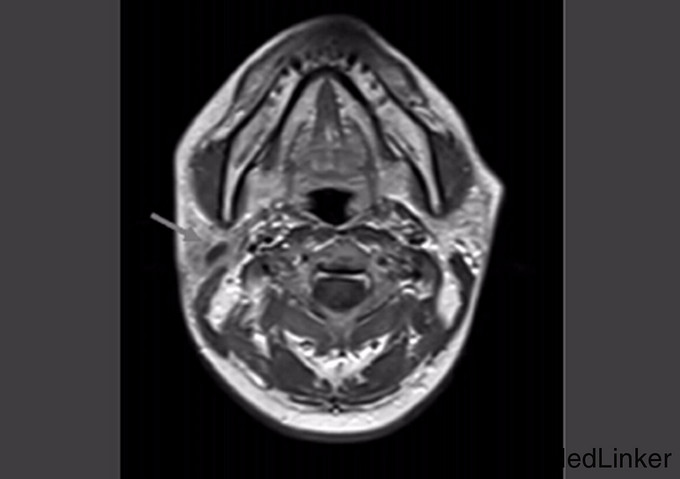

查体:右面颊腮腺区可扪及质地中等约4cm*2cm大小肿块,,界线不清,与周围组织粘连,压痛,以耳根部显著,颌下淋巴结未触及肿大,其它检查正常 辅查:超声检查:右侧腮腺内可见一个不规则低回声包块,大小约43mm*26mm*15m,边界不清,形态不规则,其内可见少许液性暗区;包块内实性部分可探及少许血流信号;MRI平扫与动态增强示:右侧腮腺区占位性病变,含囊性成分,血供欠丰富

诊断:腮腺肿块性质待查 治疗:完善相关检查后,行手术治疗:术中见肿物位于右侧腮腺下极,大小约4.5cm*4cm*2.5cm,质硬,可见部分包膜,钝性分离后完整取出。术后病理诊断:(右腮腺肿物)多形性腺瘤伴坏死,呈多结节性生长,局部细胞生长活跃,不完全除外黏液表皮样癌。